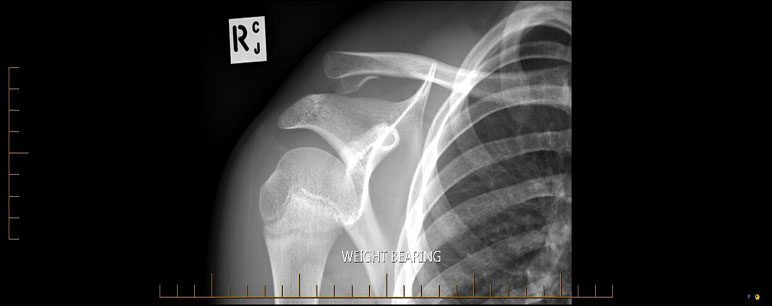

What do clavicle fractures look like on X-ray?

Below are examples of typical fractures that benefit from surgery.

What do Distal Clavicle Fractures Look Like on X-ray and CT?

X-RAY